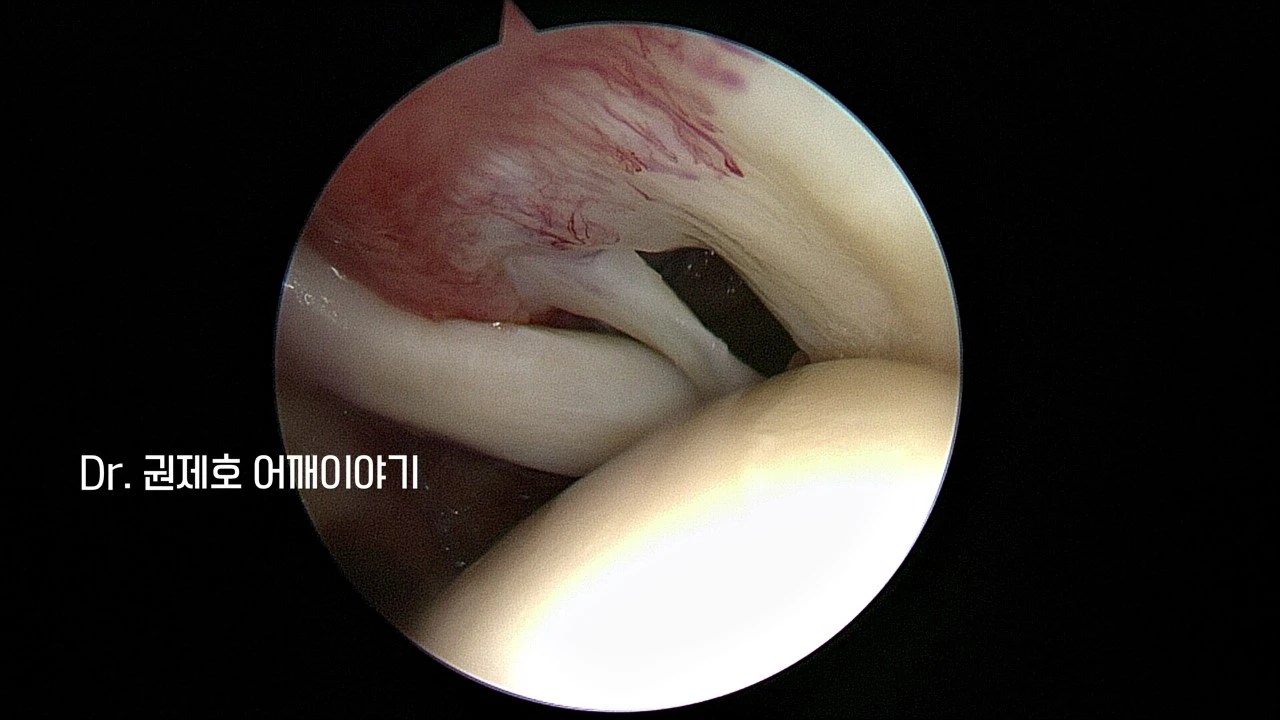

처음에는 관절에서 관찰하게 된다. 관절의 천정이 회전근개이기 때문에 관절 속에서 하늘 쪽으로 바라보면 구멍 난 회전근개가 보인다. 완전 파열을 뜻한다.